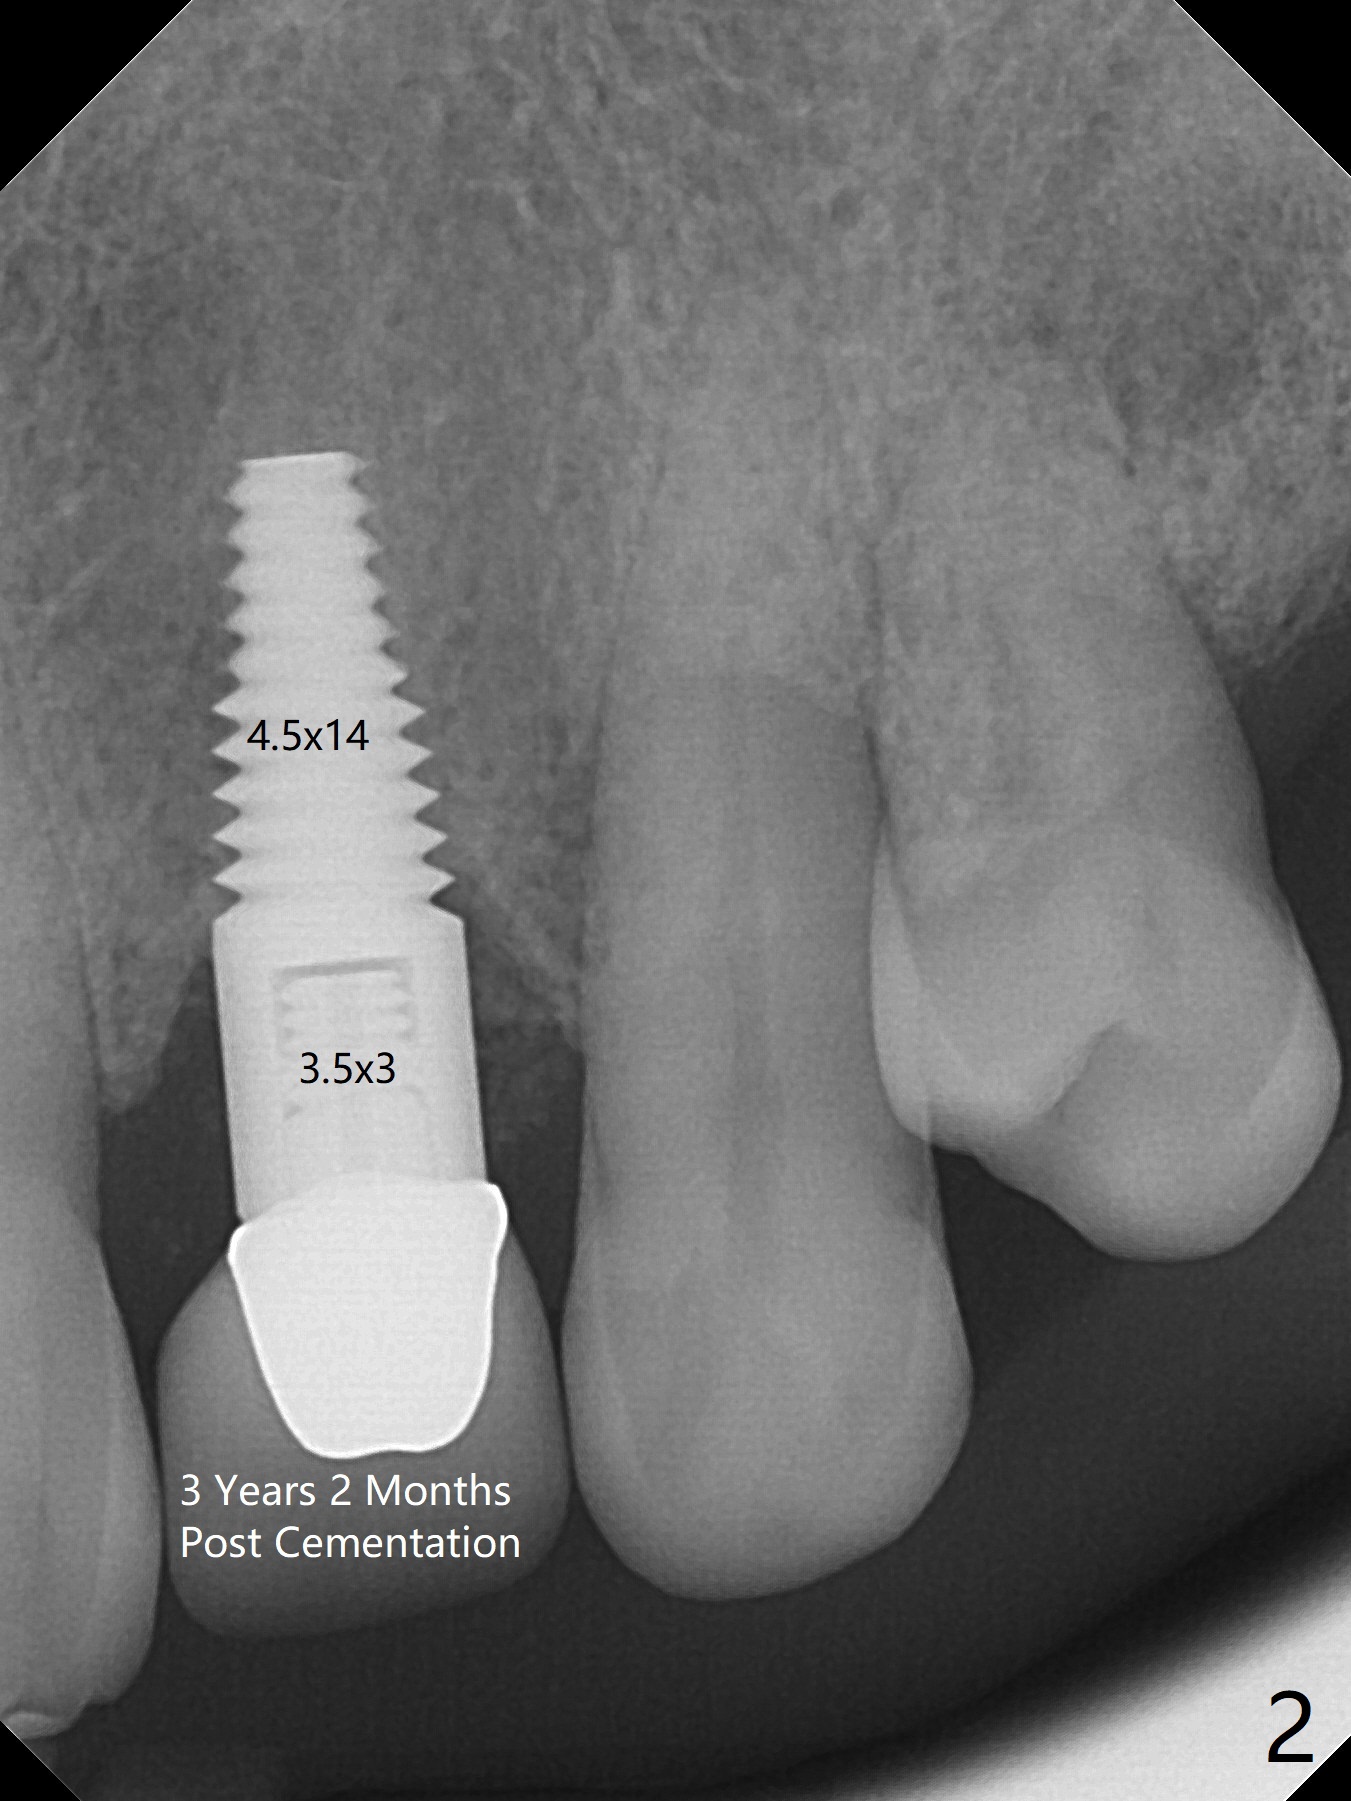

A 52-year-old woman returns for follow up 2-3 years post cementation (Fig.1-3). A smaller implant in the anterior maxilla appears to be associated with bone growth (Fig.1 * (#8)), as compared to a larger one (Fig.2 (#10)). There is apparently no bone loss at #31 (Fig.3).